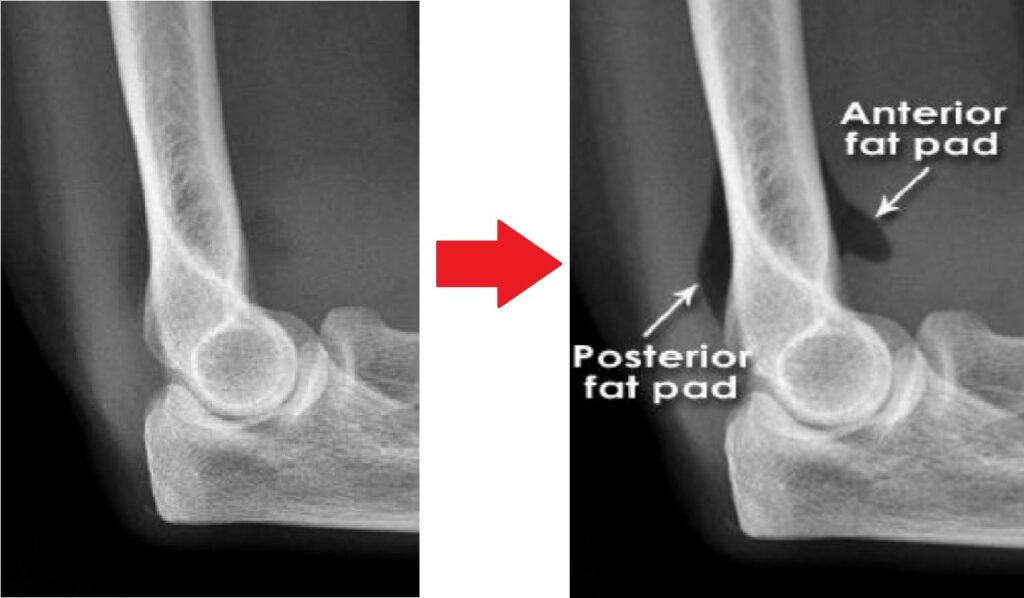

[toggle title=”Ön ve Arka Yağ Yastıkçığı Bulgusu” state=”close”]

Normalde eklem kapsülünde yağ yastıkçıkları bulunur.

Anterior yağ yastıkçığı koronoid fossada bulunur ve normal grafide de ince bir çizgi halinde görülebilir. Ancak anterior yağ yastıkçığı ayrışmış ve daha belirginleşmişse buna Yelken Bulgusu (Sail sign) denir ve görülmesi patolojiktir.

Olekranon fossada bulunan posterior yağ yastıkçığının grafide görülmesi ise her zaman patolojiktir.

Bazı non-deplase kırıklarda kırık hattı görülemeyebilir ve anormal yağ yastıkçığı işareti yaralanmanın tek bulgusu olabilir.

Travma öyküsü olan hastalarda yağ yastıkçığı görülmesi aksi kanıtlanana kadar kırığa sekonder düşünülmelidir.